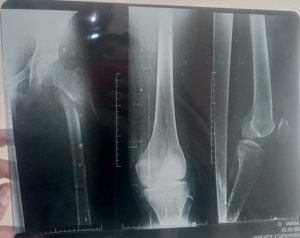

The X-ray confirmed a spiral sub-trochanteric fracture of the right femur as shown in figures 1 and 2.

Figure 1: X-Ray of right femur after fracture-posteroanterior (PA) views and lateral view

Figure 2: Post-fracture X-ray of the right femur at the hip and knee joints- PA view